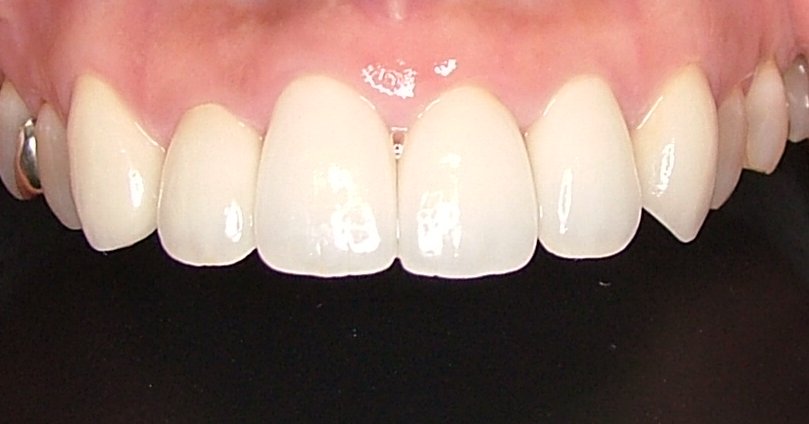

| 治療内容 | ジルコニアセラミック |

|---|---|

| 治療回数 | 2回 |

| 治療時の費用 | 363,000円 ※本症例当時の価格です。最新の費用はこちら |

| リスク・副作用 | 適切なブラッシングをしないと歯肉退縮します。 |